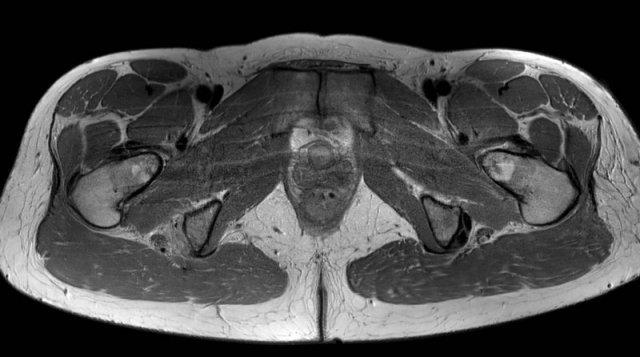

Trên ảnh MRI mặt phẳng axial này, hãy chú ý kết nối dạng cân (aponeurotic) giữa dây chằng cùng-ụ ngồi và phần nông của gân chung.

Trong một số trường hợp, các gân có thể bị bật khỏi ụ ngồi trong khi kết nối này vẫn còn nguyên vẹn. Trong những trường hợp như vậy, sẽ không có hiện tượng co rút gân và thường không cần can thiệp phẫu thuật.